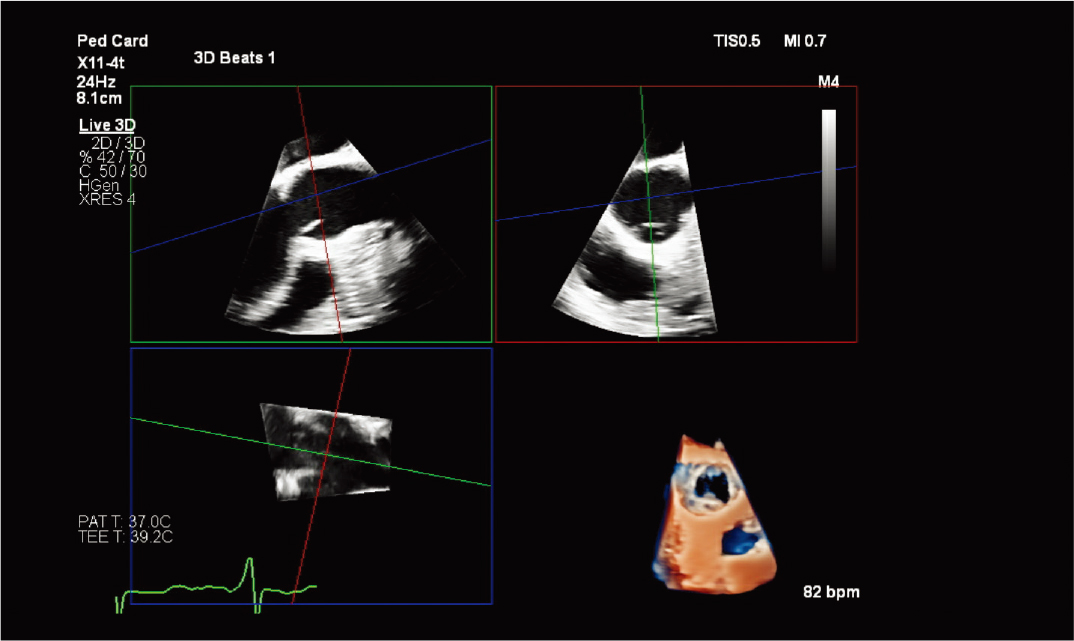

10适用于狭窄空间和复杂情况I使用全新 X11-4t 迷你 3D TEE 探头¹¹*,扩大 3D TEE 的应用范围。这款探头非常适合体型最小、体弱的患者,可扩大对儿科和成人患者的扫描范围。高效地执行手术,提高患者舒适度。X11-4t 探头与飞利浦创新产品组合集成,可与 VeriSight Pro 3D ICE** 在图像引导治疗中互补。

清晰、优质的 3D TEE 图像。

X11-4t 探头进行儿科左心耳评估 |

X11-4t 探头的儿科 3D 彩色 |